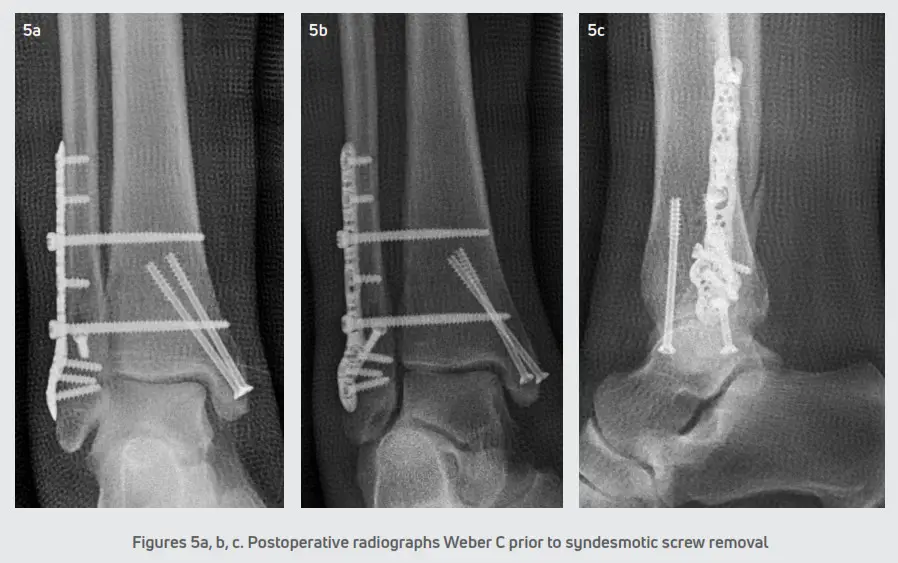

All patients were positioned supine and administered general anesthesia. In addition, patients received a popliteal block and a thigh tourniquet was utilized for hemostasis. For all fibular fractures, a direct lateral approach was performed with a linear longitudinal incision centered over the distal fibula. The fracture hematoma was evacuated and the fracture fragments were reduced with fracture reduction clamps. A solid core 3.5 mm Trilliant Gridlock ankle plating screw was placed across the fracture site utilizing standard AO principles and techniques. Then, a Trilliant Gridlock Ankle Contoured VL Fibula Plate was placed over the lateral fibula and fixated with a combination of locking and non-locking screws. The Trilliant variable angle guide was typically used in the distal fibula and screws had unicortical purchase in order to avoid violation of the tibiotalar joint. In the proximal fibula, the Trilliant static locking drill guide was used and bicortical purchase of the screw was achieved. If a medial malleolar fracture was present, then a linear longitudinal incision was made overlying the medial malleolus. The fracture hematoma was evacuated, and the fracture was manually reduced. Then, either two 4.0 mm Trilliant Tiger cannulated bone screws or a medial tibial Trilliant Gridlock ankle plate was utilized for fixation. The medial tibial Trilliant Gridlock ankle plate was placed over the medial aspect of the tibia and fixated with locking and non-locking screws. The ankle syndesmosis was stressed under fluoroscopy in all cases utilizing the Cotton hook test and/or the external rotation test. If disruption of the ankle syndesmosis was identified, a large bone clamp was used for reduction. Next, two Trilliant tapered core syndesmotic screws were placed through the ankle plate in a lateral to a medial direction crossing four cortices in order to stabilize the syndesmosis. The syndesmotic screws were typically removed approximately 8-10 weeks following the index procedure and replaced with suture button flexible fixation to maintain syndesmotic stability. Intraoperative fluoroscopy was used to confirm the anatomic reduction of the fracture and proper hardware placement. The one patient with a posterior malleolus fracture did not require internal fixation.

The incisions were closed in a standard layered fashion and a sterile, compressive dressing was applied. All patients were immobilized with a posterior splint and were initially non-weight bearing. Patients were seen for the first postoperative visit within 5-6 days for a wound evaluation. A sterile dressing and posterior splint were reapplied and patients returned at two weeks for suture removal. The postoperative course consisted of non-weight bearing in a posterior splint for 2-3 weeks. In ankle fractures with a stable syndesmosis (Figure 4), patients were transitioned into a CAM boot at 3 weeks and began protected partial weight-bearing with physical therapy. After 6 weeks, patients were transitioned to a supportive athletic shoe with an ankle brace and the final follow-up was at 12 weeks. In ankle fractures that required syndesmotic repair (Figure 5), patients were transitioned into a CAM boot and began protected partial weight-bearing at approximately 8-10 weeks. Patients were progressed into normal shoe gear at 12 weeks and aggressive physical therapy. Patients were discharged at 4-6 months and followed up as needed.